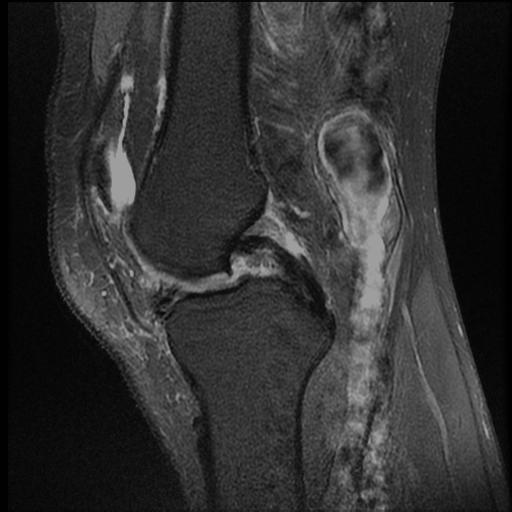

Subchondral Changes

MFC Bone Marrow Oedema and Subchondral Cyst

MFC Subchondral Oedema and Cyst